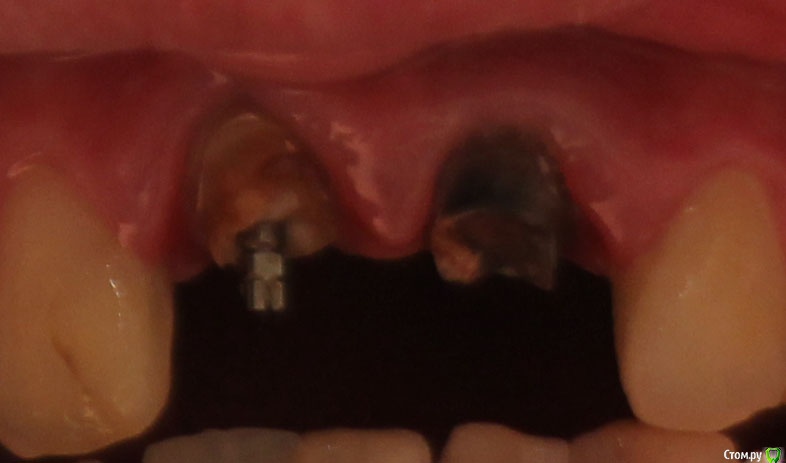

Гарикz Опубликовано 30 января, 2016 Поделиться Опубликовано 30 января, 2016 Добрый день, хотел бы услышать мнение профессионалов что делать дальшеВ детстве было неправильное лечение 2х верхних центральных зубов, они по какой то причине потемнели. Решили их сточить и одеть на них металлокерамику. Пролечили, в один зуб поставили штифт. Прошло 5 лет, коронки выпали, посоветовавшись, просто зацементировали их и забыли. Прошел год и проблема повторилась. Скажите пожалуйста что можно сделать в данной ситуации? Читал про культевую вкладку, как думаете , поможет? Форма металлокерамики очень нравится и не хотелось бы изготавливать новую, вообщем нужен ваш совет. Фото прилогаю (к сожалению на данный момент качество не очень) Ссылка на комментарий

Гарикz Опубликовано 31 января, 2016 Автор Поделиться Опубликовано 31 января, 2016 Загрузил фото нормального качестваИмпланты нужно делать сразу 2 зуба и немедленно, по финансам 100 000 прям сейчас не могу потянуть, в перспективе можно импланты, но по хорошему хотябы через пару лет. Неужели без них сейчас не обойтись? Ссылка на комментарий